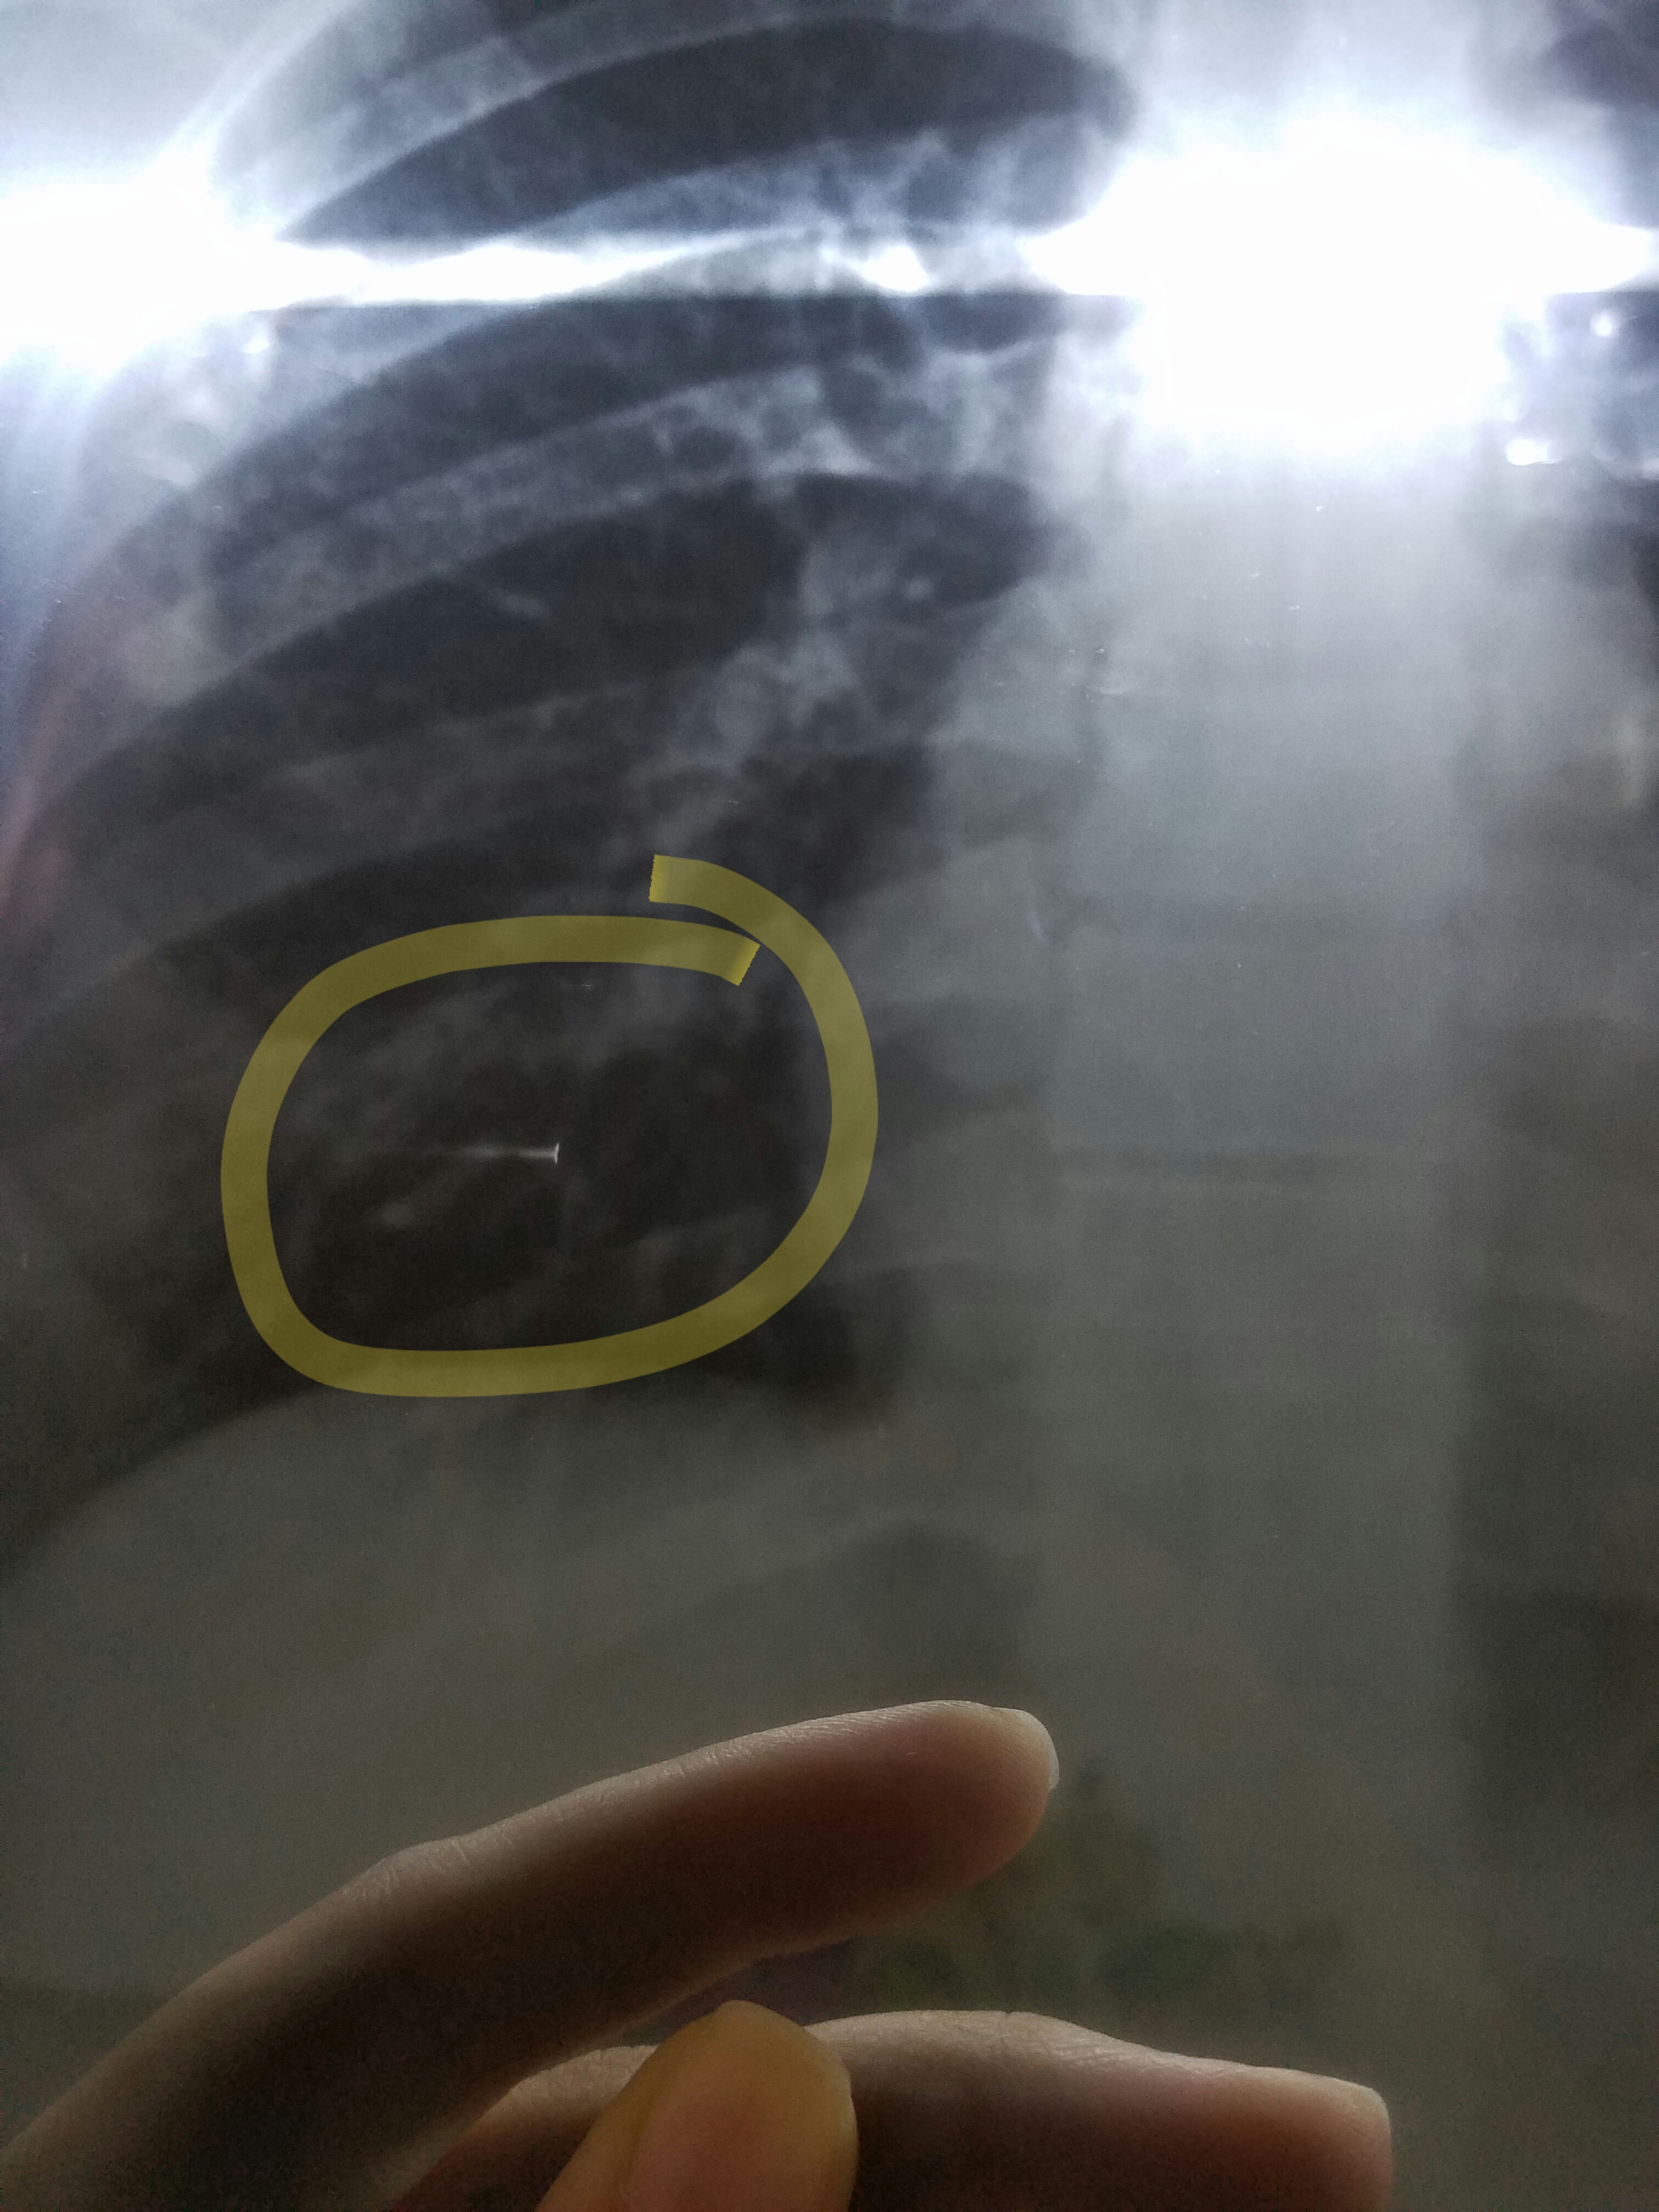

Is this shadow in my chest xray something to worry about? The doctor I consulted said that it is an xray defect though I do feel pain in the right side of my chest.

It’s foreign body particle probably. Plz repeat XRay and check pulmonologist.